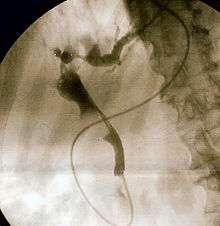

The gold standard test for biliary obstruction is still endoscopic retrograde cholangiopancreatography (ERCP). This involves the use of endoscopy (passing a tube through the mouth into the esophagus, stomach and thence to the duodenum) to pass a small cannula into the bile duct. At that point, radiocontrast is injected to opacify the duct, and X-rays are taken to get a visual impression of the biliary system. On the endoscopic image of the ampulla, one can sometimes see a protuberant ampulla from an impacted gallstone in the common bile duct, or the frank extrusion of pus from the common bile duct orifice. On the X-ray images (known as cholangiograms), gallstones are visible as nonopacified areas in the contour of the duct. For diagnostic purposes, ERCP has now generally been replaced by MRCP. ERCP is only used first-line in critically ill patients in whom delay for diagnostic tests is not acceptable; however, if the index of suspicion for cholangitis is high, an ERCP is typically done to achieve drainage of the obstructed common bile duct.[1]